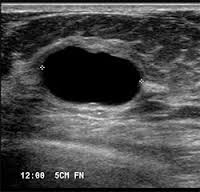

простая киста молочной железы.